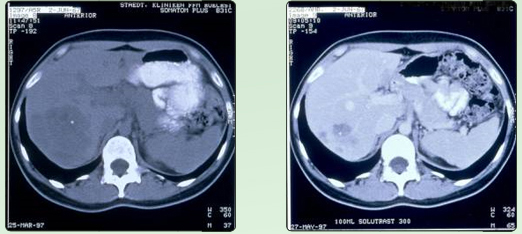

Lebermetastasen vor RTH - Lebermetastasen nach RTH

Lebermetastasen bei Mamma C A

progrediente Lebermetastasen bei metastasierenden Mamma-CA ( ED.1/96 ) unter systemischer Chemotherapie (4xEC). Nach 6 maliger 1 stündiger regionaler Tiefenhyperthermie unter Beibehaltung der Chemotherapie wurde eine 80%ige Partialremission (Teilrückbildung) erreicht; aus

Mastall H. Zeit- und situatiosgerechte Einsatzmodelle für komplementäre Verfahren während

konventionell-onkologischer Therapien:

32. Medizinische Woche Baden-Baden 1998; 02.XI